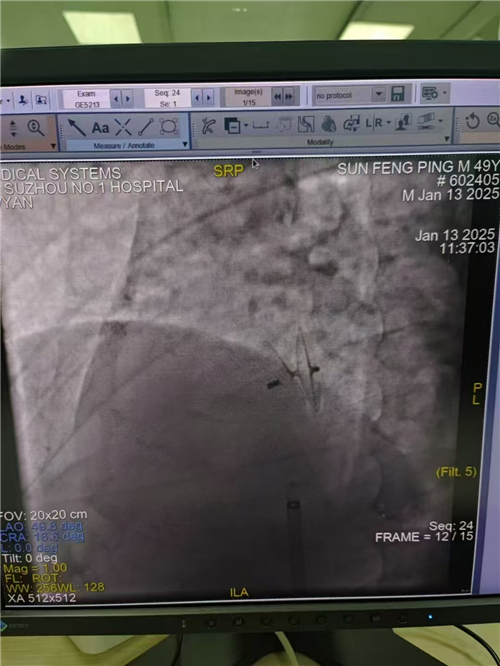

手术当天,主刀医生周博文与超声科、麻醉科团队紧密协作,仅用 20 分钟就成功在封堵部位释放封堵器。经超声心动图检查显示,未见残余分流,封堵器位置固定,二、三尖瓣启闭良好,房室及大动脉水平也未见明显分流束。多学科的高效协作不仅极大地提高了手术质量与效率,也增强了医护人员之间的默契。术后,孙先生病情平稳,脑梗及头痛、头晕症状消失,仅两天便康复出院,对治疗效果十分满意,现已恢复正常生活。